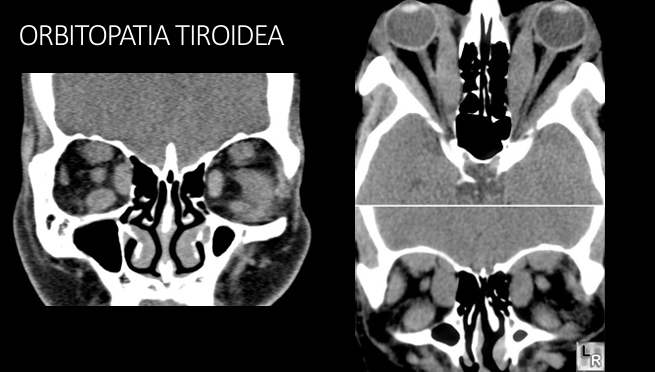

3

Q

Imagen en orbitopatia tiroidea

A

Agrandamiento bilateral de músculos extraoculares

4

Tc en orbitopatia tiroidea

Agrandamiento músculos extraoculares, exoftalmos, nervio óptico estirado

5

RM en orbitopatia tiroidea

T1: agrandamiento músc extraoculares

T2: aumento señal en musculos extraoculares en fases agudas

Diametro disminuido nervio óptico